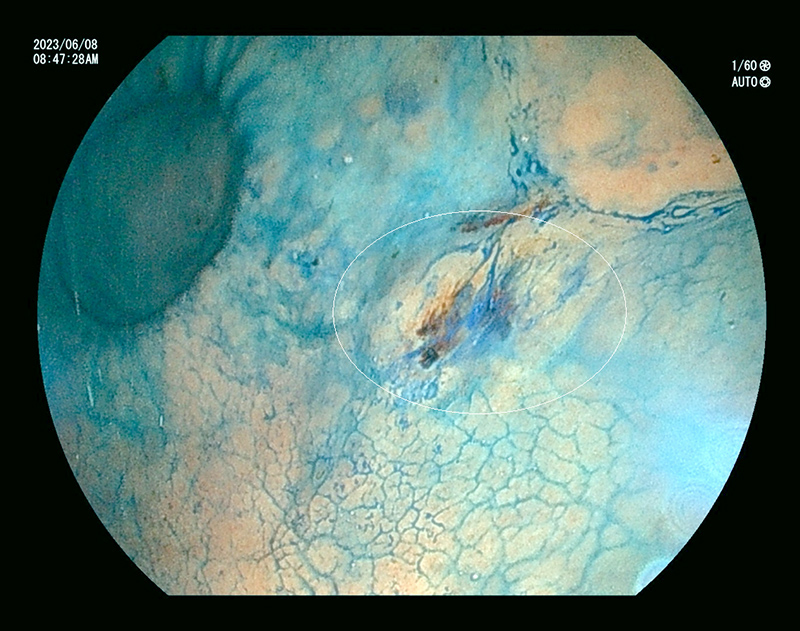

内視鏡検査の所見例

発赤した食道癌

食道と胃の境 食道炎

胃体部 アニサキス虫体

胃体部 胃癌

大腸ポリープ

通常光(白色光)

通常光では淡い発赤ですが

特殊光-1

同じところを空気量調整し特殊光LCIにて観察

特殊-2

同じところを特殊光BLIにて血管と表面構造を観察

内視鏡検査の所見例

発赤した食道癌

食道と胃の境 食道炎

特殊光で炎症を強調して観察

胃体部 アニサキス虫体

アニサキス虫体を取り去った後の腫れた粘膜

胃体部 胃癌